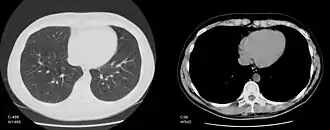

КТ-снимок грудной клетки в лёгочном и мягкотканном окнах (на изображениях указаны параметры центра и ширины окна)

Обычный компьютерный монитор способен отображать до 256 оттенков серого цвета, некоторые специализированные медицинские аппараты способны показывать до 1024 оттенков. В связи со значительной шириной шкалы Хаунсфилда и неспособностью существующих мониторов отразить весь её диапазон в чёрно-белом спектре, используется программный перерасчёт серого градиента в зависимости от выбранного интервала шкалы. Чёрно-белый спектр изображения можно применять как в широком диапазоне («окне») денситометрических показателей (визуализируются структуры всех плотностей, однако невозможно различить структуры, близкие по плотности), так и в более-менее узком с заданным уровнем его центра и ширины («лёгочное окно», «мягкотканное окно» и т. д.; в этом случае теряется информация о структурах, плотность которых выходит за пределы диапазона, однако хорошо различимы структуры, близкие по плотности). Изменение центра окна и его ширины можно сравнить с изменением яркости и контрастности изображения соответственно.